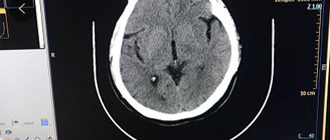

飛利浦CT維修—飛利浦MX-16slices CT維修案例

一、故障現象 1、掃描病人時,系統有時自動重啟或是藍屏。 2、可以做球管預熱,但不能做STUDY掃描,報錯提示:機架錯誤,請重啟機架或主控臺計算機。 二、 維修情況說明 ...

飛利浦MX16排CT維修案例分享2

1、掃描病人時,系統有時自動重啟或是藍屏。2、可以做球管預熱,但不能做STUDY掃描,報錯提示:機架錯誤,請重啟機架或主控臺計算機。3 維修情況說明3.1? 分析故障產生原因? 3.1.1 軟...